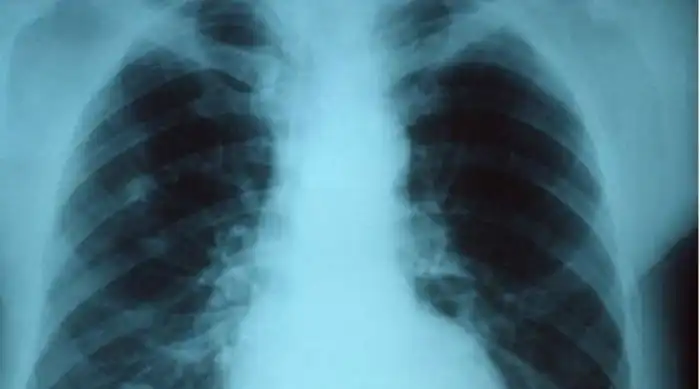

Воспаление легких

Воспаление начинается из-за белых кровяных клеток различных типов, которые, вообще-то, занимаются уничтожением вируса в вашей крови. Воспаление — иммунная реакция на все виды проблем, от вирусов и бактерий до физических травм. Это не проблема для краткосрочных инфекций, а вот с гриппом ситуация другая. К примеру, в легких опухоль может препятствовать проникновению кислорода в кровеносные сосуды. Постепенно легкие просто начинают разрушаться от недостатка кислорода. Развившаяся из-за вируса гриппа опухоль легких может убить человека очень быстро. Иногда хватает всего двух-трех дней, притом все происходит достаточно неожиданно для самого пациента.

Вторичная инфекция

Вирус гриппа будто открывает ворота прочим инфекциям. Подхватить что-то в дополнение к этому вирусу — проще простого. Чаще всего развивается пневмония, опасная и сама по себе. Так происходит потому, что иммунная система не имеет ресурсов, чтобы одновременно сражаться с гриппом и держать заслон против бактерий, которых у каждого из нас более, чем достаточно. Бактерии начинают бесконтрольно размножаться, развивается так называемая вторичная инфекция. Если она затрагивает легкие, пневмонии не избежать.